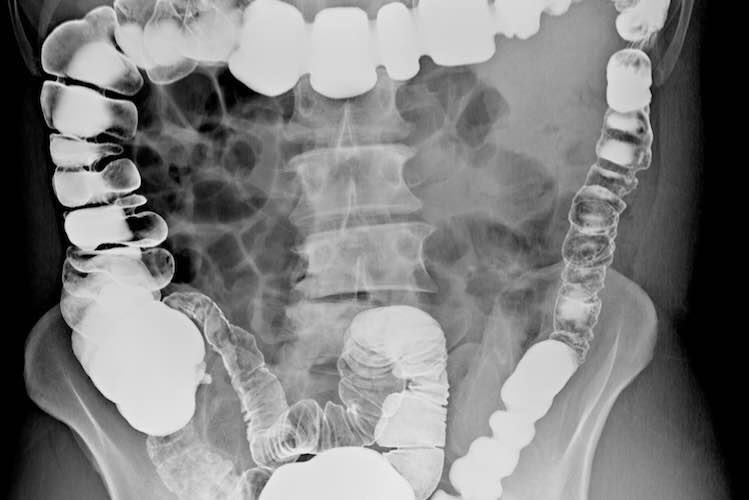

هو مرض مزمن يصيب الأمعاء الغليظة و يسبب تقلصات و انتفاخات في البطن (البطن منتفخ) ، يمكن أن يؤثر على أي شخص في أي عمر ، و تختلف أعراضه بين المصابين بهذا المرض و يُصنف هذا المرض ضمن منطقة الجهاز الهضمي كما هو موضح بالصورة: